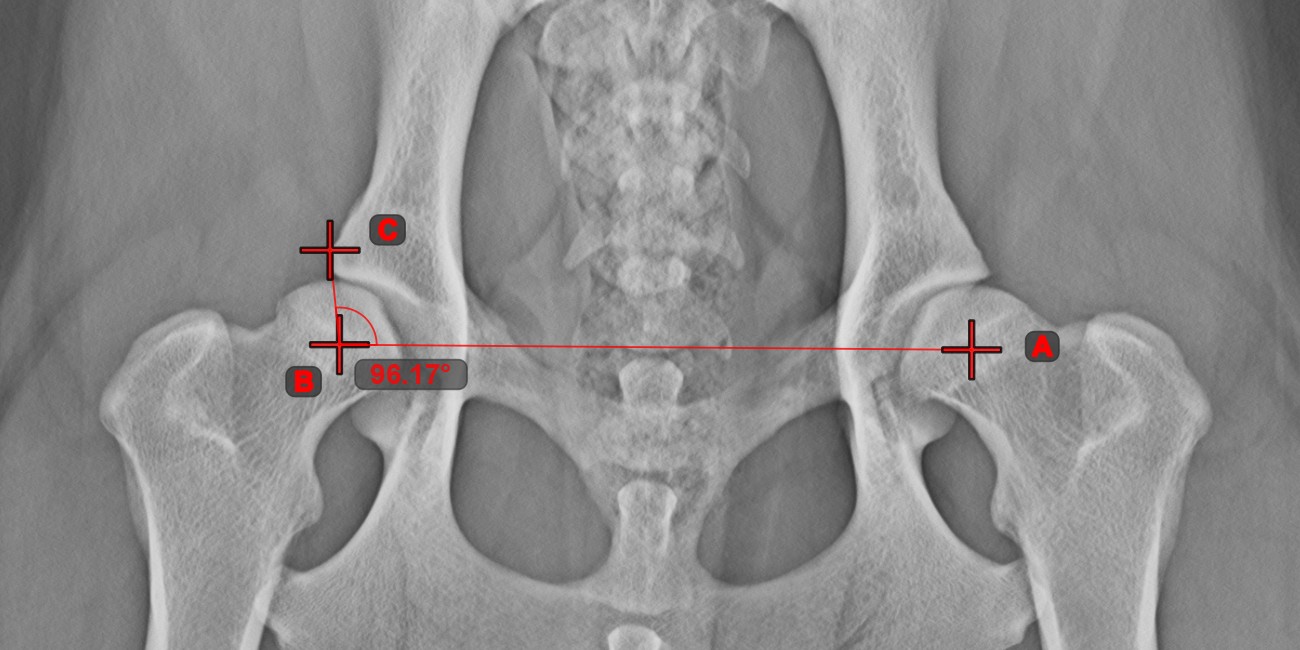

Angle of Lines¶

Select the tool from the left toolbar and assign it to one of the available mouse buttons. Start by selecting the first line from the ones already drawn on the scene, or place the start and end points to create the line. Follow the same steps for the second line of the measurement. The angle between the two lines will be automatically calculated.

Modify the start and end points of both lines by using the Select/Move Item tool. The angle between the two lines will be automatically recalculated.

Information

If two lines do not intersect directly, the angle of their extended projections on the scene will be calculated.

Angle from 3 Points¶

The Angle from 3 Points tool is a simple and effective way to calculate an angle from just three points.

Start by selecting the tool from the left toolbar and assign it to one of the available mouse buttons. Place the start point of the initial side, the vertex, and the end point of the terminal side of the angle, or select the points from the scene. The sides of the angle will be automatically constructed, thus calculating the angle between the lines.

Modify the position of the three points to change the arc of the angle by using the Select/Move Item tool.